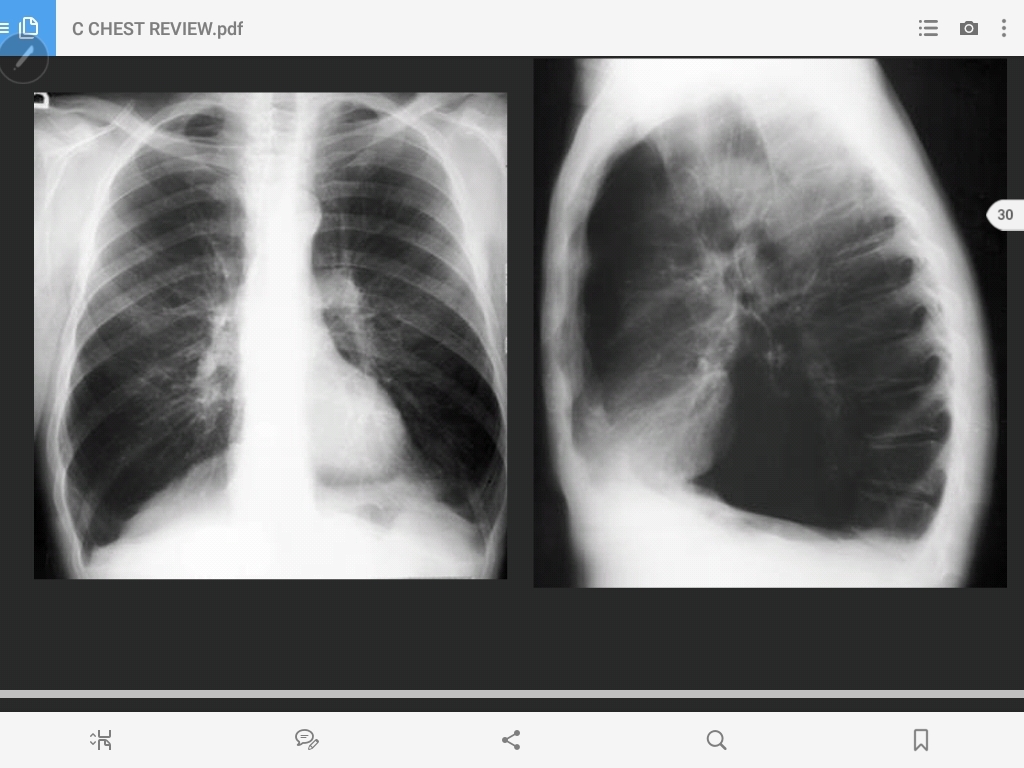

pneumonia of the left upper lobe

lingular pneumonia